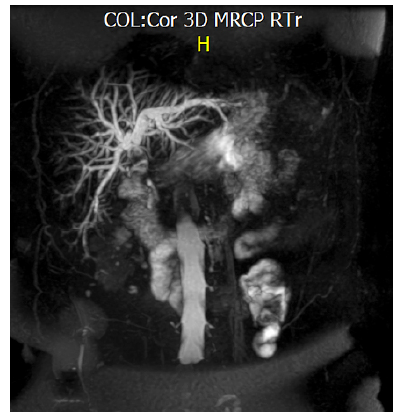

For its part, MRC showed generalized dilation of the intrahepatic and extrahepatic bile ducts, common bile duct with an average dilatation of 1 cm, with presence of hyperintense faceted images in T2. Gallbladder was not identified (Figure 1).

MRC - 3D reconstruction of the coronal section in the bile duct. Note the absence of gallbladder.

Figure 1: MRC - 3D reconstruction of the coronal section in the bile duct. Note the absence of gallbladder.

Source: Own elaboration based on the data obtained during the study.

However, despite the fact that postoperative ERCP/MRC should inevitably be performed, in this case, MRC should always be considered, since agenesis is an exotic pathology and the infrequent vesicular positions mentioned above can be overlooked 3-5,7-14, thus avoiding, in the first instance, the risks of ERCP when there is no lithiasis in the primary bile duct (choledocholithiasis) (Figure 3). However, in the presence of agenesis, ERCP has been reported as not effective due, in part, to dysfunction of the sphincter of Oddi, so many patients need surgery and lithotripsy, as happened in this case 15.

3D reconstruction of the bile duct. Note the multiple hyperintense images, the major ones (yellow arrow) correspond to lithiasis of the bile duct.

Figure 3: 3D reconstruction of the bile duct. Note the multiple hyperintense images, the major ones (yellow arrow) correspond to lithiasis of the bile duct.

Source: Own elaboration based on the data obtained in the study.